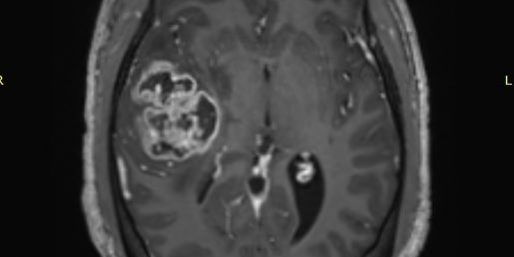

Χωροκατακτητική Εξεργασία δεξιού Κροταφικού Λοβού